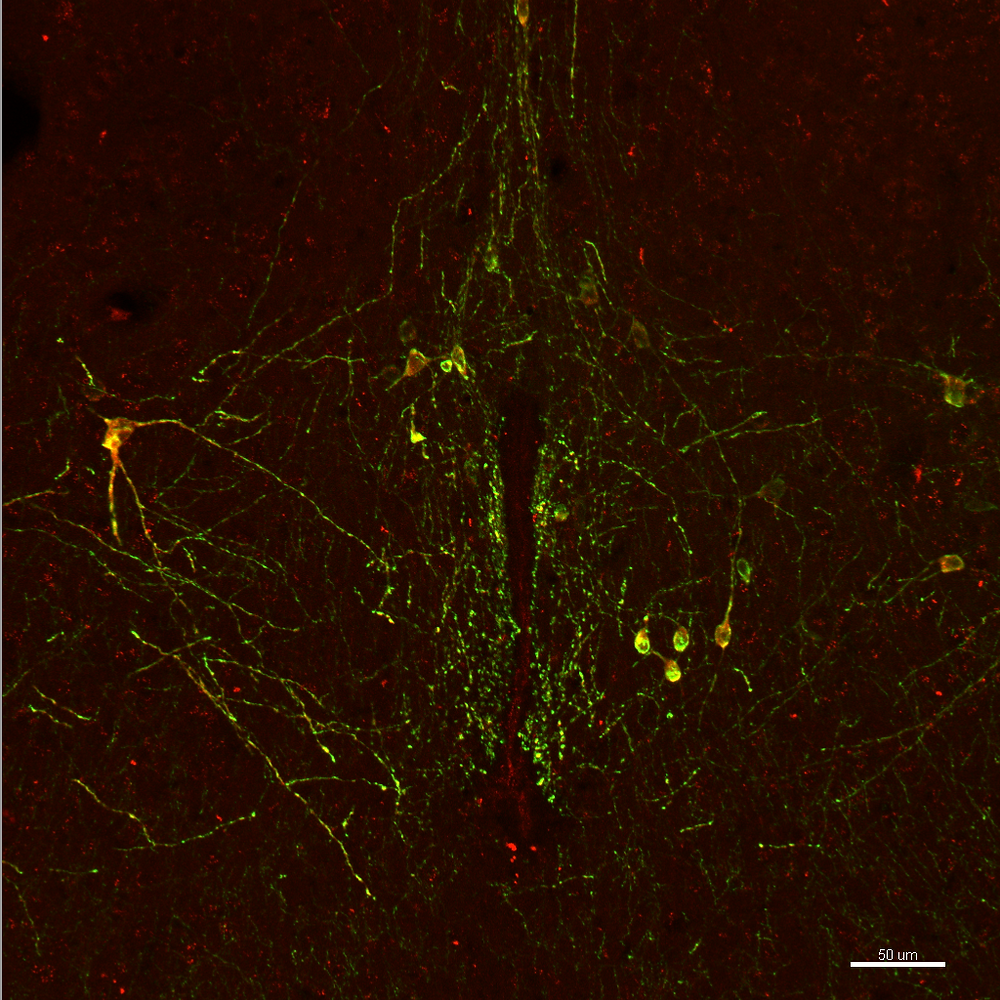

The Neuroscience of Sub Space in BDSM - Endorphins, Noradrenaline and Serotonin